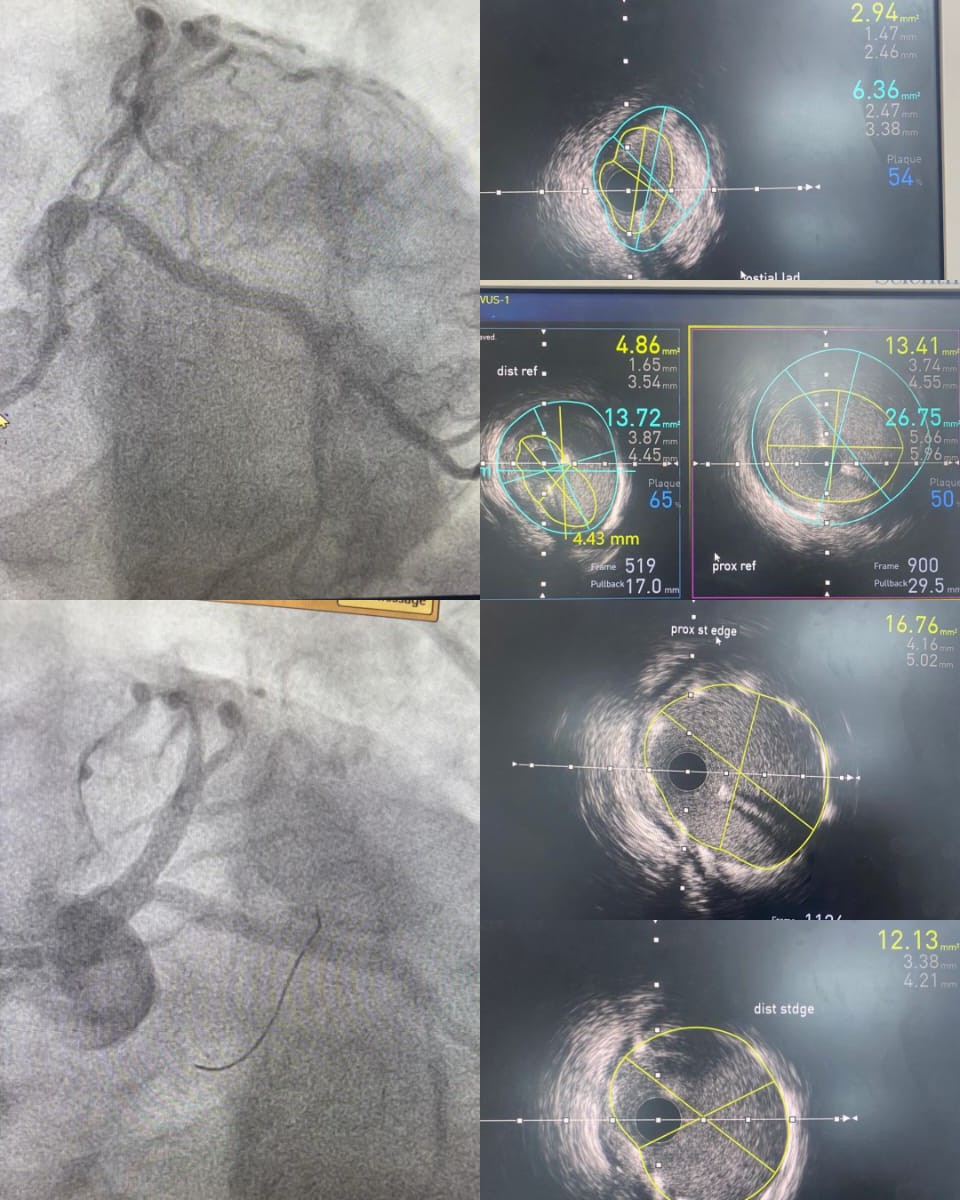

*IVUS-Guided Left Main to LAD Precision Angioplasty at NAMCO Hospital*

A 60 male presented with a strongly positive TMT. Coronary angiography revealed a *distal left main (LM) plaque and critical 90% stenosis at the ostium of the left anterior descending artery* (LAD).

Given the complex anatomy and high-risk location, the patient underwent a precision PCI using IVUS guidance—from the left main to the LAD successfully